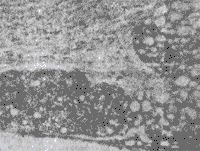

实验组家兔8只的血管内膜均可见不同程度的淡黄色斑块,以主动脉弓、腹主动脉及肾主动脉分叉处较明显,脂肪染色显出明确的红色斑块,组织切片HE染色,动脉内膜弥漫增厚,有的呈丘状突向管腔,内膜下有较多泡沫细胞和少量成纤维细胞及胶原(图1)。冠状动脉和心肌内血管内膜增厚更严重并纤维化、玻璃样变、管腔闭塞(图2)。实验组大鼠20只和所有对照组家兔及大鼠的冠状血管及主动脉等的内膜光滑、未见明显异常,脂肪染色阴性,HE染色动脉各层结构清楚完好。

Fig 2 The AS plaque of arteriole inside the cardia muscle of rabbit after 42 d with hypercholesterol feeding,The vascular wall thicken seriously with fibrosis and hyaline degeneration,which occluded the lumen of vessel.HE 12.6×10

图2 高脂饲料喂养42 d后家兔心肌内动脉内膜的AS斑块